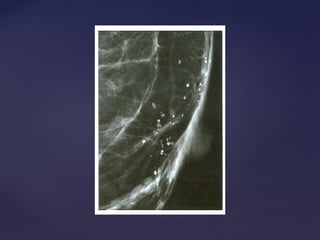

Descrição dos achadosDescrição dos achados

Calcificações

1.Morfologia das partículas

2.Distribuição do agrupamento

Puntiforme Redonda Anelar Em bastão Grosseiras heterogêneas Pleomórficas finas Amorfas tênues Lineares

Agrupadas Lineares Segmentares Regionais Esparsas